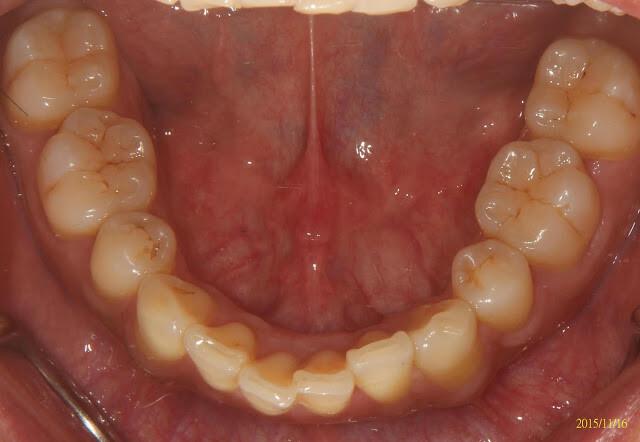

透明維持器(clear oerlay)口內照,跟隱形牙套很像吧

透明維持器(clear overlay),跟隱形牙套很像吧